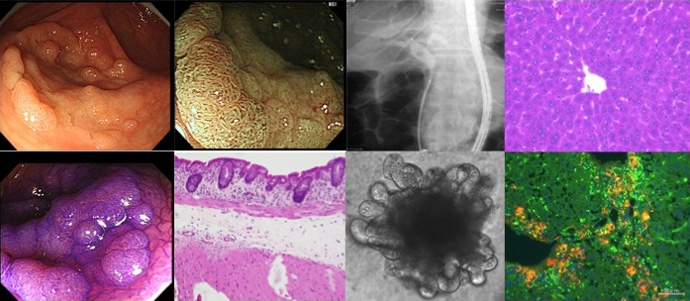

当分野では、肝再生の分子機構の解明や肝障害に対する肝細胞増殖因子(hepatocyte growth factor:HGF)の有効性の検証など,障害肝組織の再生・修復および炎症性発癌に関する研究を行ってまいりました。近年では、消化管,胆膵疾患や腎疾患の腫瘍や慢性炎症に対する基礎、臨床研究を積極的に行っています。

| 研究テーマ | 肝再生、肝発癌、消化管粘膜の再生・修復 |

| 研究テーマ | 腸疾患の病態解明 |

| 研究テーマ | 消化器(炎症性疾患・がん)免疫、IgG4関連疾患・自己免疫性膵炎の診断・治療・病態解明 |